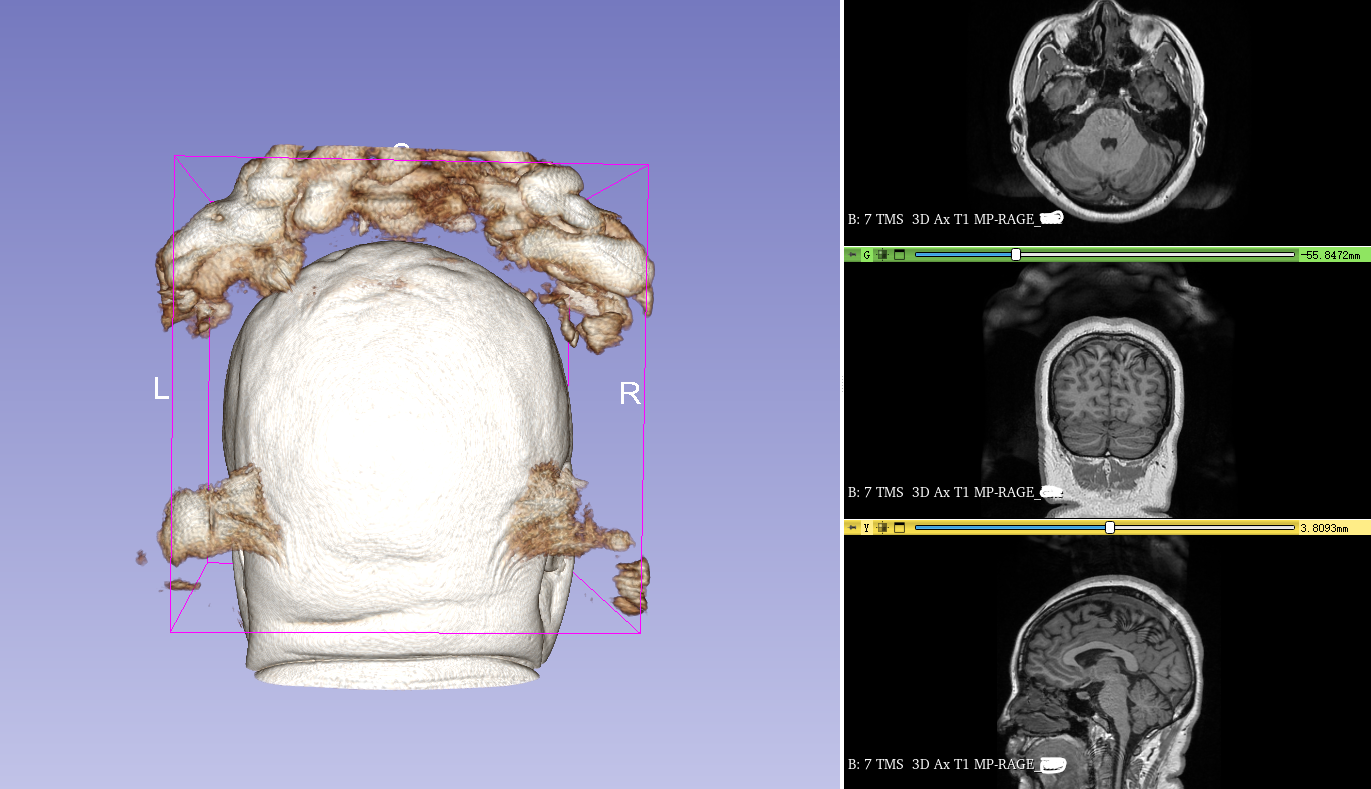

背景:有一个被试数据头顶有很多干扰,直接覆盖在头颅核磁影像上非常影响处理和视觉效果

如下图,头骨周边被很多阴影块覆盖了(预估扫描时没有排除干扰),我想重新得到干净只有头颅的核磁影像。

还是有很多杂乱的东西包裹着头颅,此时就需要剪刀工具了。

这个剪刀工具很神器,只能在3D 视图中操作,而且做的是立体裁剪,我们需要小心谨慎地用剪刀裁剪掉头颅周边的杂快,可以多做几次,改变视角和方向直到把杂块都剪干净,要是不小心操作错了就得灵活运用 “撤销” 功能,然后继续,直到剪干净。

如下图可以看到修剪前后的变化。